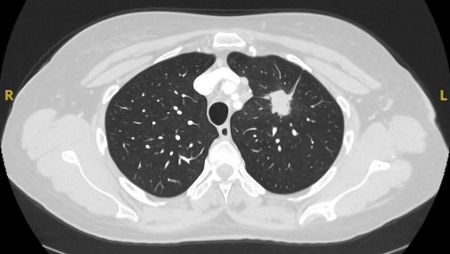

[Figure caption and citation for the preceding image starts]: PET-CT com 18-fluordesoxiglucose (18-FDG) mostrando lesão periférica de alta captação no pulmão esquerdo. A ressecção cirúrgica confirmou câncer pulmonar de células escamosas moderadamente diferenciadoDo acervo de Dr. George Tsaknis, MD, PhD, FRCP (Londres), MRQA, MAcadMEd, PGCert; usado com permissão [Citation ends].